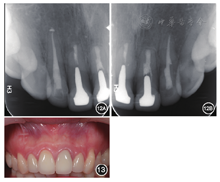

根尖3 mm倒充填致密见图8,图9,图10,图11。分别于术后3、6个月时复查根尖X线片,8个月时复查锥形束CT并分别进行临床检查。复查结果显示

根尖病变已愈合,

根尖无明显低密度影。临床检查

叩诊正常,无松动,牙龈位置无明显变化。

根尖X线片 A:

根尖病变明显缩小;B:

根尖病变明显缩小

根尖病变愈合;B:

根尖病变接近愈合

根尖病变已愈合

根尖病变已愈合重新制作临时冠确保美观及冠方封闭良好。根尖病变愈合后,

叩诊正常,不松动,牙龈色泽正常,切口位置可见隐约瘢痕。根尖X线片显示

根尖无明显病变。

根尖无明显病变;B:

根尖无明显病变